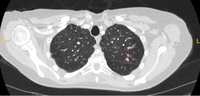

Cortes de tomografia computadorizada (TC) com exemplos de nódulos solitários semissólidos

Do acervo de Dr. George Tsaknis, MD, PhD, FRCP (Londres), MRQA, MAcadMEd, PGCert; usado com permissão